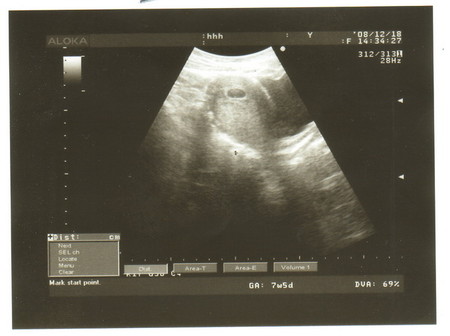

Очень рада за тебя.Поздравляю!!!!!!!!!Береги себя и фасолинку твою,она у тебя очень мило выглядит.